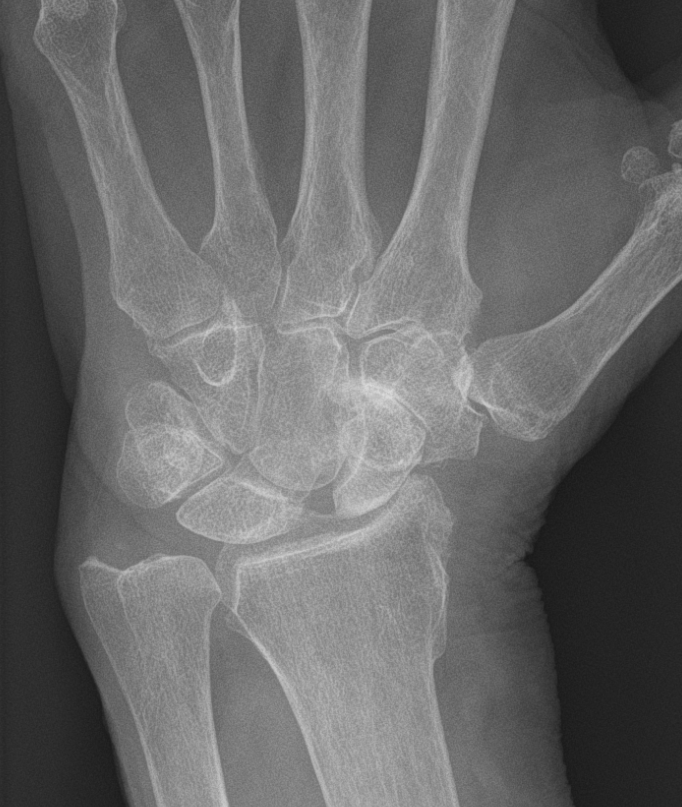

3. Scapholunate widening